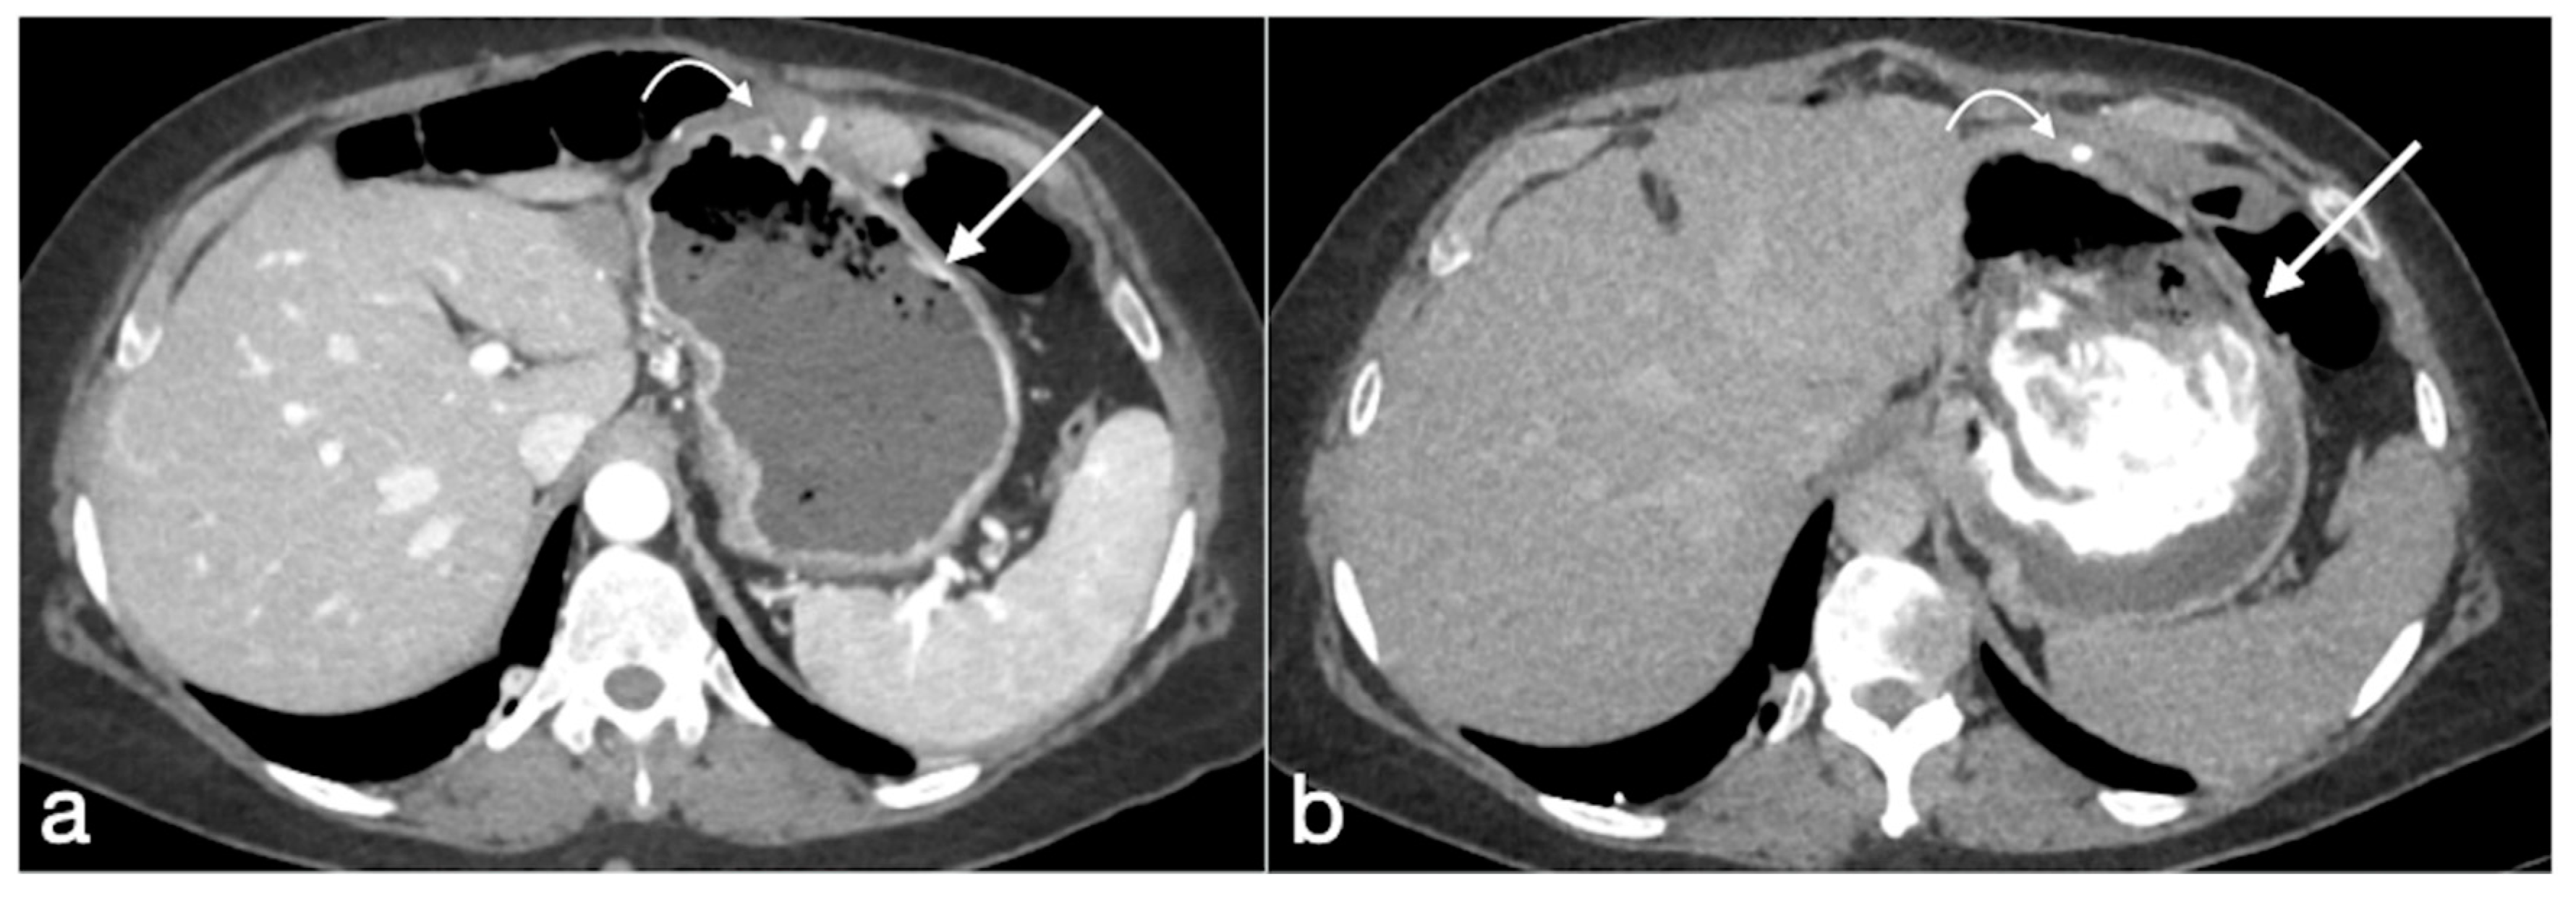

Figure 20. Patient 2. Suture leak with spleen abscess after sleeve gastrectomy. A 48-year-old patient underwent sleeve gastrectomy and complained in the following days of abdominal pain, fever, and dyspnea. At the first CT examination is seen the leak (a, axial view, straight arrow), free peritoneal fluid (a, curved arrow) and inhomogeneous enhancement of the spleen (a, circle). In more cranial scans, a splenic abscess is seen (b, circle) associated with the reactive pleural effusion (b, curved arrow), and the coronal view (c) further clarifies the finding (c, circle, splenic abscess). It was decided that the patient should be managed with percutaneous drainage of the splenic abscess. The patient came back after the drainage positioning, with chest pain and dyspnea (df) and at CT the left anterior pneumothorax (d, axial view, curved arrow) was detected due to the drainage positioning, which is actually in the splenic abscess (e, axial view, circle). However, in its course it crosses the left diaphragm (f, coronal view, circle).